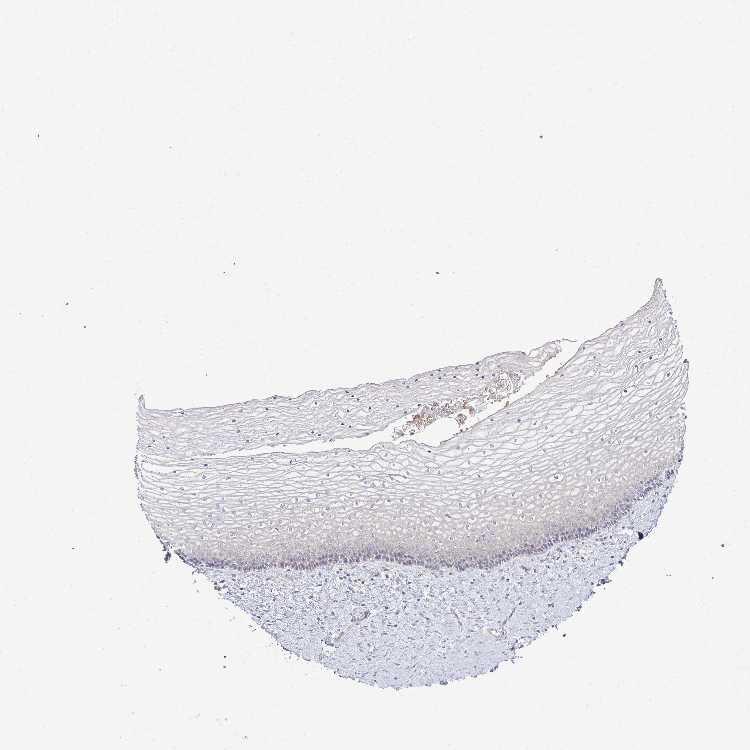

Antibody HPA059235

Squamous epithelial cells Low